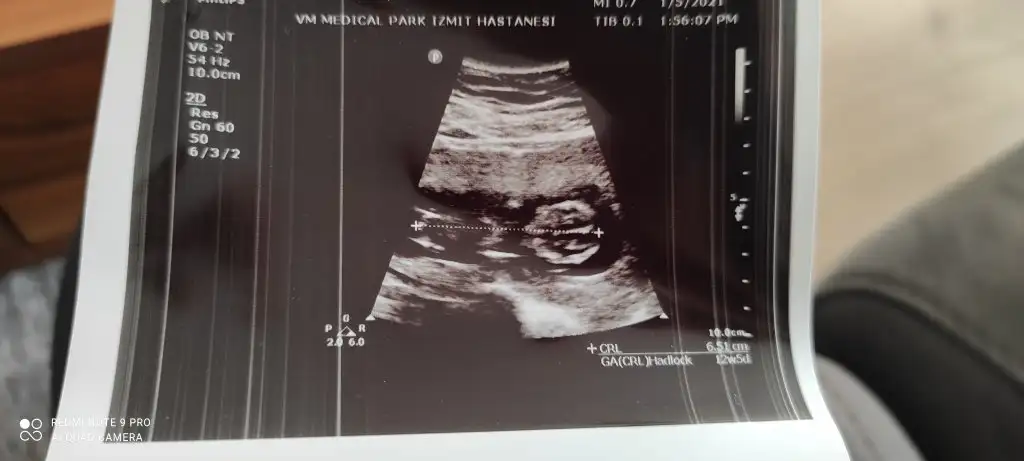

Geçen hafta da bakmıştık doktor da sen de kıza benziyor demiştin Ikra meyra :) Ama bugün doktor erkeğe benziyor dedi tam belli olmuyor nubu tek ultrason fotoğrafı var bugünden ama bir denemek istedim bakalım bugün ne diceksin :)

Ölçümün hemen yanında nubu yüksek görünüyor 12+5 gore erkek görünüyor

Ben mi göremiyorum ya çizip göndermen mümkün mü acaba rica etsem :) Ben sanki arkası dönük gibi görüyorum ondan anlayamadım :) Doktorla orantılı gidiyor tahminleriniz bakalım :)

Bir de bana yorum yapar mısın? Gönderdiğim fotolar sat a göre 12+3 ultrasona göre 13+1.